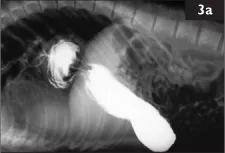

Clinical examination revealed no abnormality and the animal was within normal weight range for the stage of rehabilitation. All standard blood parameters were normal. Plain radiographs of the chest and abdomen were unremarkable. 150 ml of barium contrast medium was delivered into the caudal oesophagus via gavage tube and a radiograph (3a) taken within five minutes.

i. What can you see on the radiograph?

ii. What is your diagnosis?

3 i. A diaphragmatic hernia of the cardiac area of the stomach. A dilated caudal oesophagus, lightly outlined by barium and filled with air, is also visible.

ii. Diaphragmatic hernia and megaloesophagus (confirmed on necropsy, 3b).